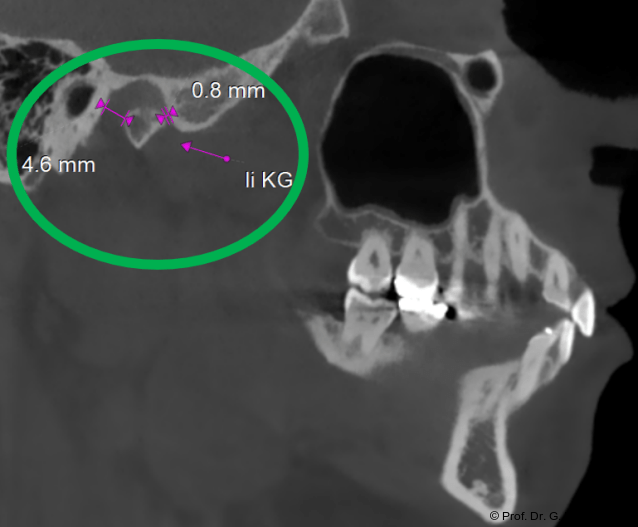

Im Sagittalschnitt zeigen beide Kiefergelenke eine deutlich anteriore Position. Der dorsokraniale Abstand betrug rechts 7,0 mm und links 5,8 mm. In der PEP waren sie im lateralen Bereich ca. 1 mm kleiner als in der Mitte der Sagittalprojektion (Abb. 6a–d).

Diese deutlich anteriore Gelenkposition im Neutralbiss ließ den Verdacht auf einen Sunday Bite zu. Das heißt, die Patientin schob den Unterkiefer aktiv nach vorne, um damit schönere Schneidezahnkontakte bzw. eine vermeintlich neutrale Okklusion zu erreichen. Nach mühsamen Lockerungsübungen gelang es der Patientin, auch in die zen­trale Kiefergelenkposition zu wechseln. So zeigte sich das ganze Ausmaß der Malokklusion. In neutraler KG-Position hatte die Patientin eine sagittale Frontzahnstufe von ca. 7 mm mit 1 PB Klasse II-Okklusion im Seitenzahn­bereich (Abb.5a+b, 7a–c).

Nach der Umstellungsosteotomie mit der UK-­Vorverlagerung kann die Patientin besser zubeißen. Bei maximaler Interkuspidation in neutraler Okklusion befinden sich nun beide Kiefergelenke in zentraler Po­sition zur Gelenkpfanne. Der geringe Abstand des Caput mandibulae zur Schädelgrube lässt auf eine Diskusverlagerung schließen (Abb. 20a+b).